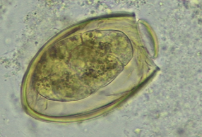

Paramigonus westermani ova

Paragonimus westermani

40X magnification